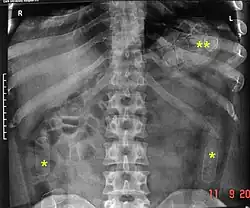

Routine detection of the smuggled packets is extremely difficult, and many cases come to light because a packet has ruptured or because of intestinal obstruction. Unruptured packets may sometimes be detected by rectal or vaginal examination, but the only reliable way is by X-ray of the abdomen. Hashish appears denser than stool, cocaine is approximately the same density as stool, while heroin looks like air.[11][12]

An increasingly popular type of swallowing involves having the drug in the form of liquid-filled balloons or condoms/packages. These are impossible to detect unless the airport has high-sensitivity X-Ray equipment, as a liquid mixture of water and the drug will most likely not be detected using a standard X-Ray machine. Most of the major airports in Europe, Canada, and the US have the more sensitive machines.